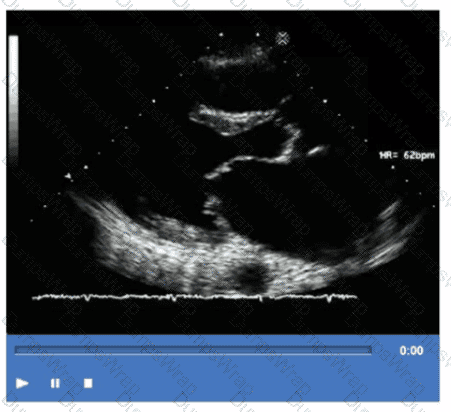

Which step is next in further evaluation of the abnormality shown in this video?

Options:

Administration of agitated saline with cough

Administration of agitated saline from right antecubital vein

Administration of agitated saline with Valsalva maneuver

Administration of agitated saline from left antecubital vein

Answer:

CExplanation:

Comprehensive and Detailed Explanation From Exact Extract:

The video suggests an atrial septal abnormality possibly a patent foramen ovale or interatrial shunt. To evaluate for right-to-left shunting across an atrial septal defect, the administration of agitated saline contrast with a Valsalva maneuver is the next best step.

Valsalva increases right atrial pressure transiently, promoting transient right-to-left shunting, making microbubbles visible in the left atrium if a shunt is present. Administration without Valsalva reduces sensitivity. The choice of arm vein (right or left) is less critical.

This diagnostic technique is well described in ASE adult congenital heart disease guidelines and echocardiography contrast protocols【12:ASE Contrast Echocardiography Guidelines†p.190-195】【16:Textbook of Clinical Echocardiography, 6e†p.575-580】.